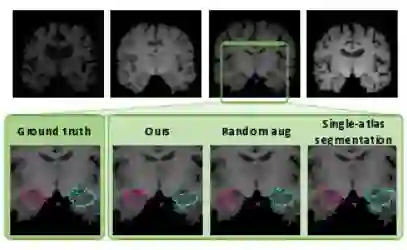

图1:生物医学图像在解剖结构,对比度和纹理方面经常变化很大(顶行)。与其它one-shot分割方法(底行)相比,我们的方法能够更准确地分割解剖结构。

为了克服这些挑战,许多有监督的生物医学分割方法专注于人工设计预处理步骤和架构。使用手动调整的数据增强来增加训练样本的数量也很常见,诸如随机图像旋转或随机非线性变形之类的数据增强功能,并且已被证明在某些例子中有效地提高了分割准确度。然而,这些功能模拟多样化和现实的例子的能力有限,并且可能对参数的选择高度敏感。